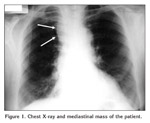

A 63-year-old woman visited her physician because of 3-months history of headache and fatigue. She denied changes in her voice, dyspnea, dysphagia, or musculoskeletal pain. There was no relevant medical or family history. Physical examination was normal. Abnormal calcium and phosphate levels were detected in blood analysis and abnormal right upper mediastinal shadow on chest x-ray film was detected (Figure 1).